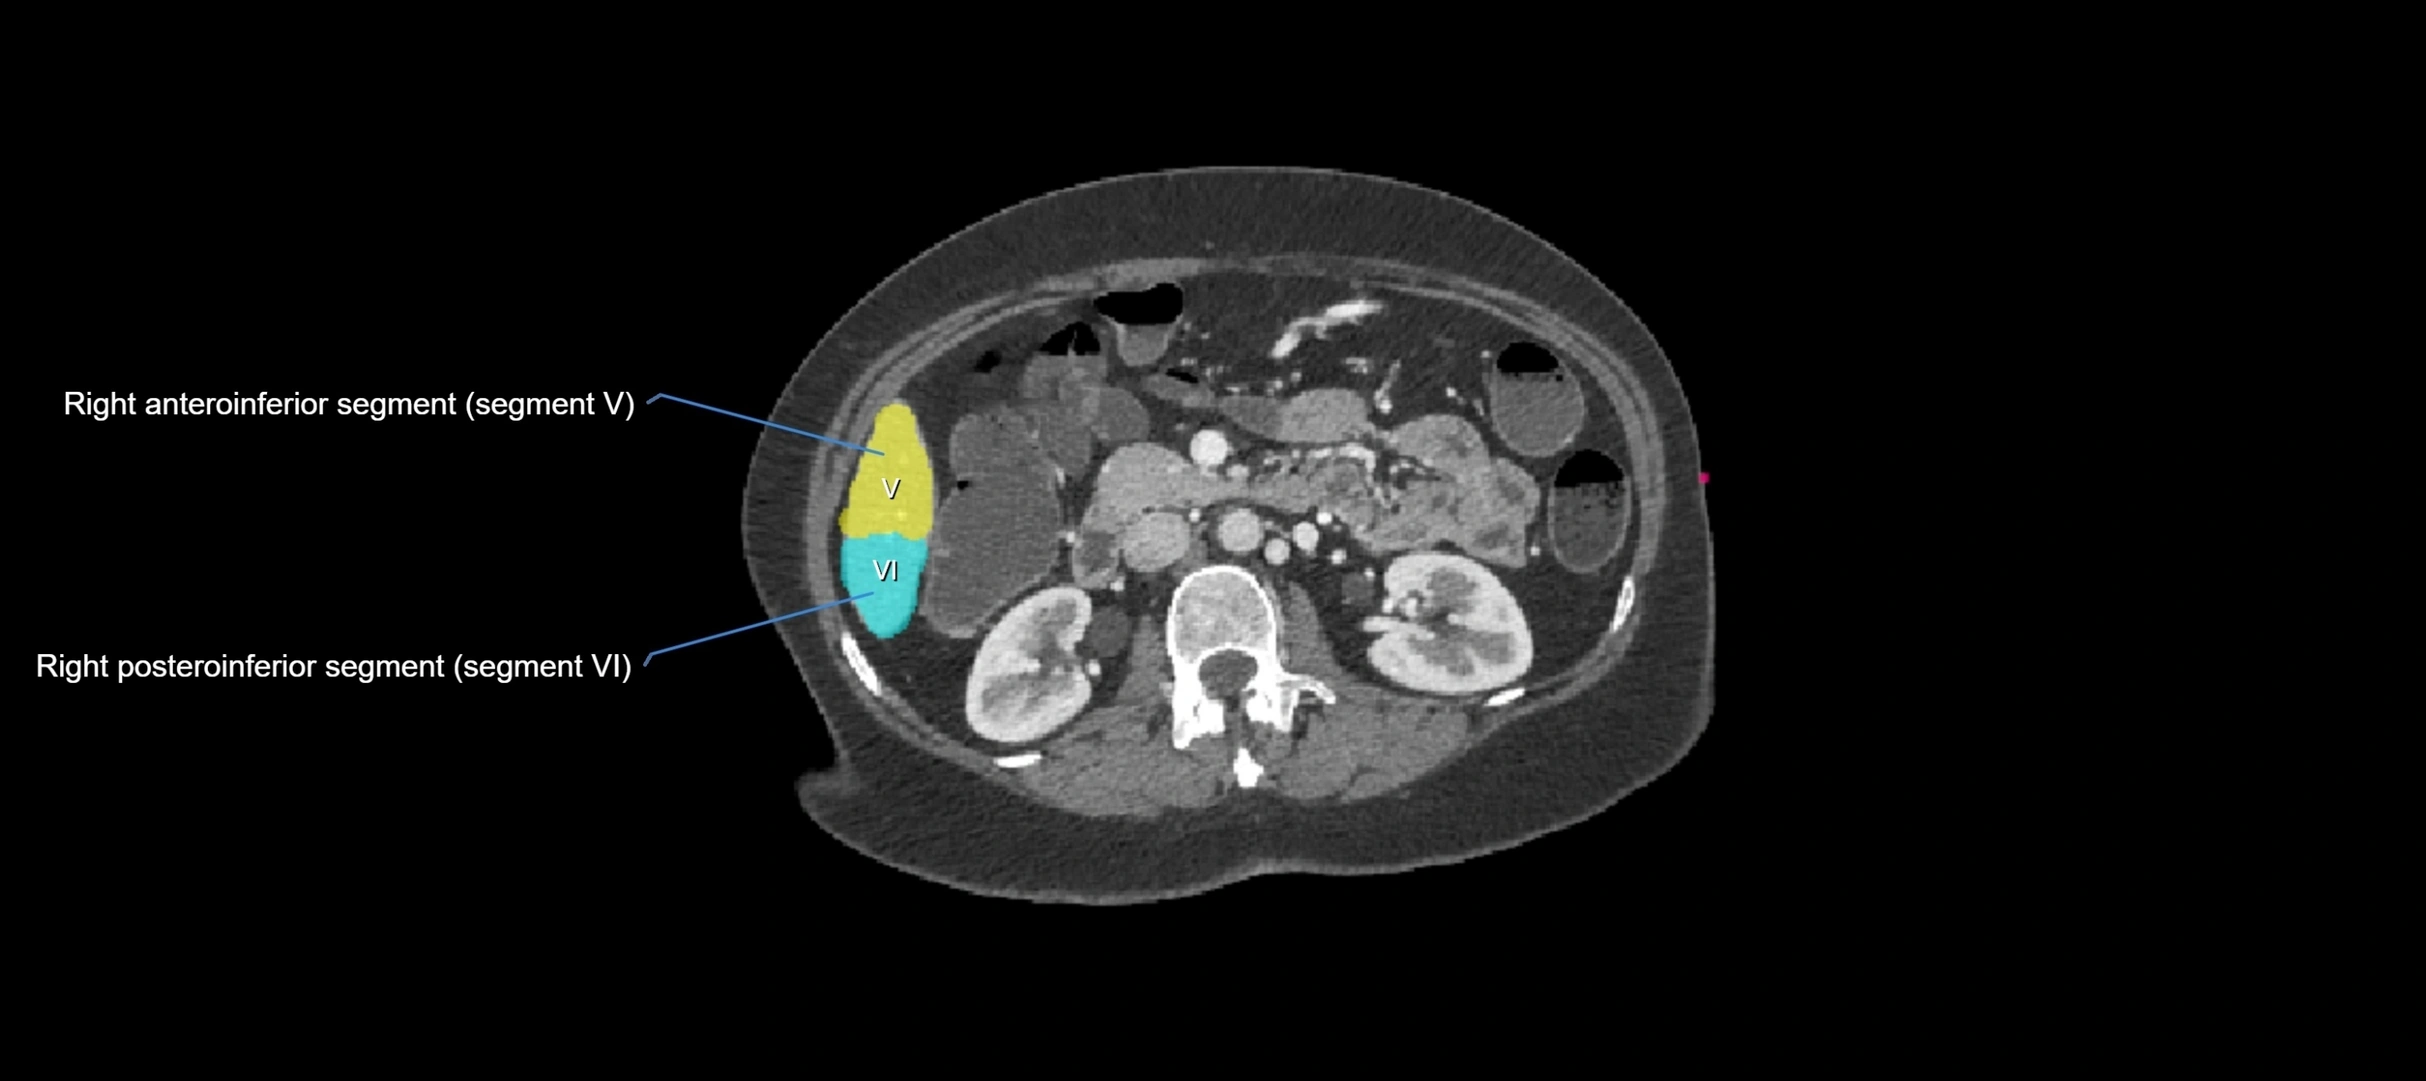

CT Image

image